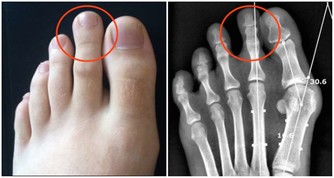

有些家長擅自給孩子添補維生素D,孩子“吃不消”,就可能會出現精神狀態異常,如煩躁、失眠、半夜啼哭,以及食慾不振、噁心嘔吐、腹瀉,甚至腎結石、血尿等問題。